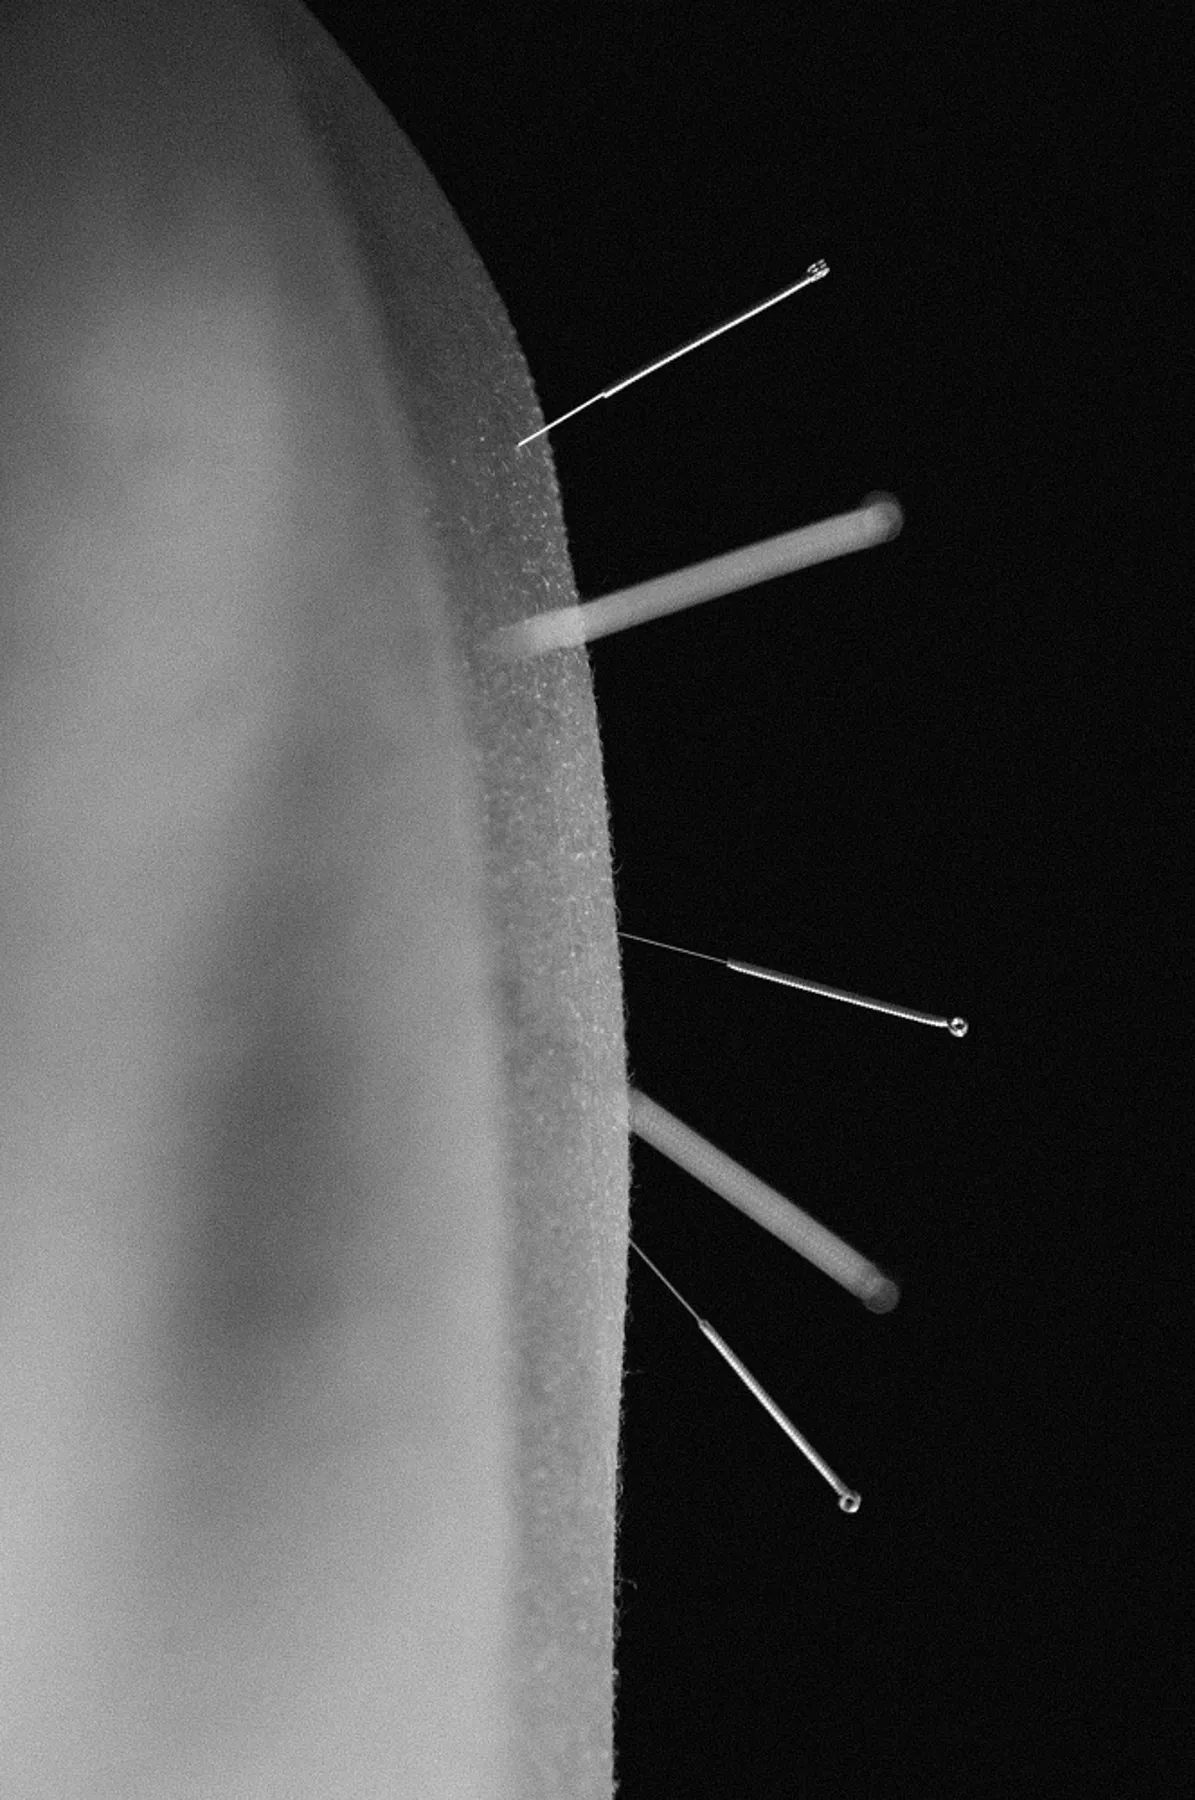

We create a personalized treatment plan designed to address your unique needs. This plan may include a combination of acupuncture, cupping, gua sha, body work, moxibustion, and electro-acupuncture, as well as diet and lifestyle homework to keep you going between sessions.

Acupuncture therapy

60 min—Initial Acupuncture Session

Your gentle anti-aging journey

Touted as a natural face lift, facial rejuvenation acupuncture, uses tiny needles to stimulate collagen, reduce wrinkles, and give you a bright and glowing complexion. This treatment is for those seeking to avoid aggressive approaches and treat their skin with grace.

60 min—Facial Rejuvenation Acupuncture